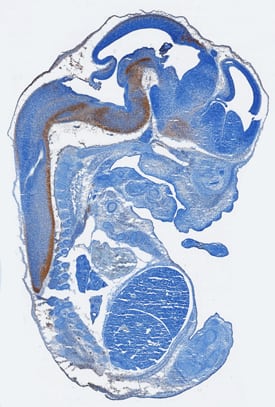

HB-EGF antibody in Mouse Embryo by Immunohistochemistry (IHC-Fr).

HB‑EGF in Mouse Embryo.

HB-EGF was detected in immersion fixed frozen sections of mouse embryo (15 d.p.c.) using Sheep Anti-Mouse HB-EGF Antigen Affinity-purified Polyclonal Antibody (Catalog # AF8239) at 15 µg/mL overnight at 4 °C. Tissue was stained using the Anti-Sheep HRP-DAB Cell & Tissue Staining Kit (brown; Catalog # CTS019) and counterstained with hematoxylin (blue). Specific staining was localized to developing central nervous system. View our protocol for Chromogenic IHC Staining of Frozen Tissue Sections.